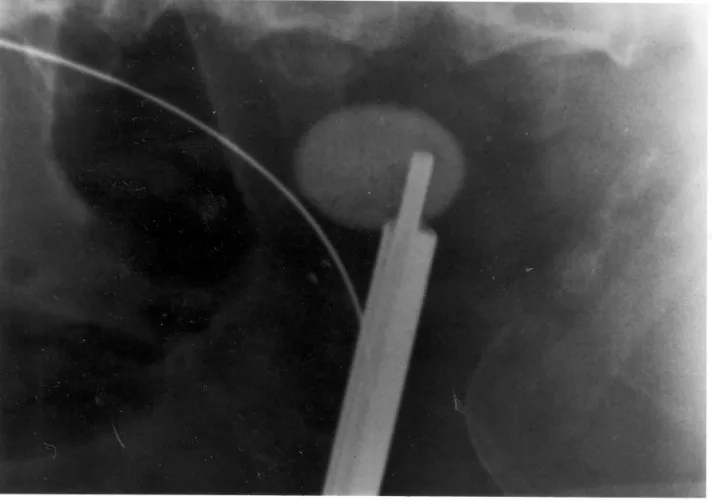

Vesekő Vesekő Nagyméretű vesekő és a hozzá vezetett ultrahangos zúzóeszköz röntgenfelvételen. Kategória Diagnosztika Közzétéve: 2016. 04. 23. 14:55